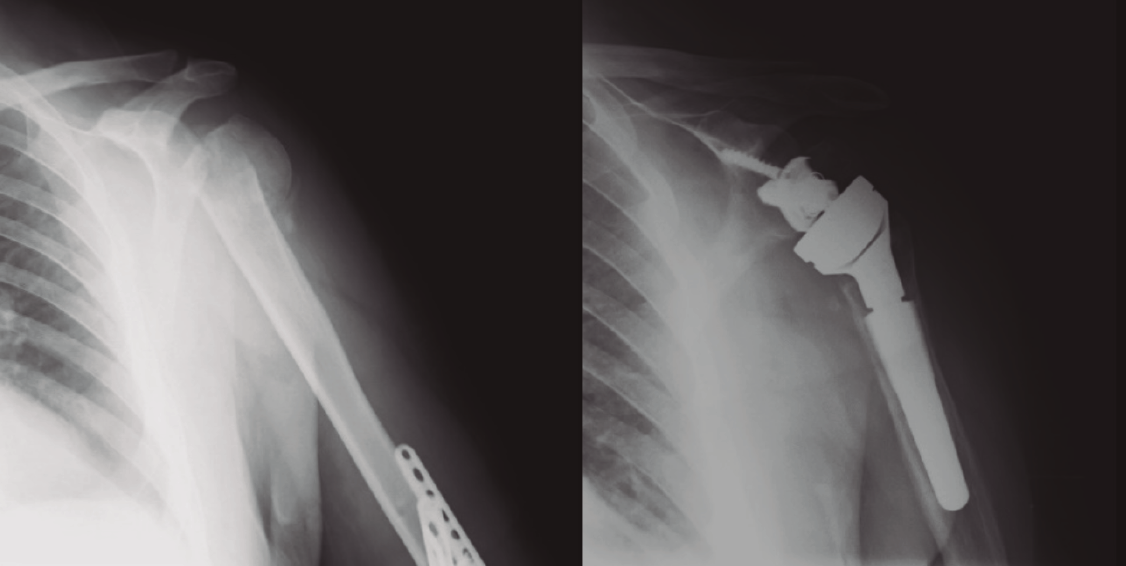

Figura 9. Radiografía de una fractura de húmero pre- y posprótesis invertida.